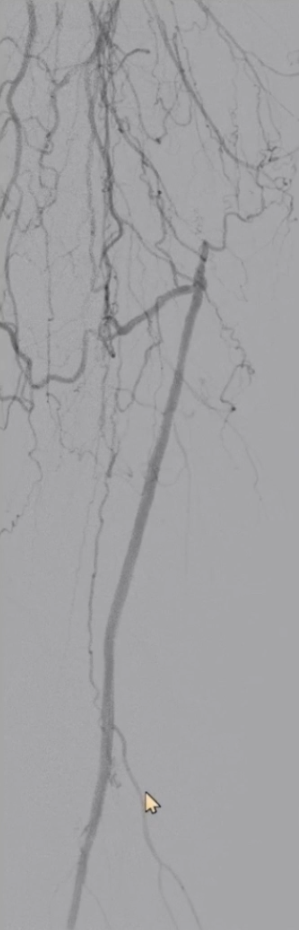

6

手术结果:

血流通畅,解剖与功能双重改善

最终造影显示:支架定位准确、形态良好,股浅动脉、腘动脉及膝下动脉显影清晰,血流通畅。